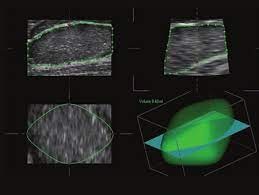

- 3D/4D možnosti: Pokročilé zobrazení pro OB/GYN aplikace.